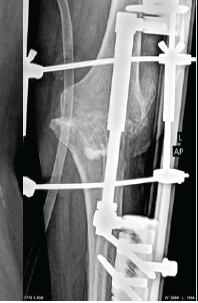

Knee Arthodesis, As a Salvage Procedure for Non-union of Floating Knee after Ilizarov Fixation-A Case Report

Harsh Kumar , Raj Suhas Kamble , Suhas Laxman Kamble

………………………………p.239-243